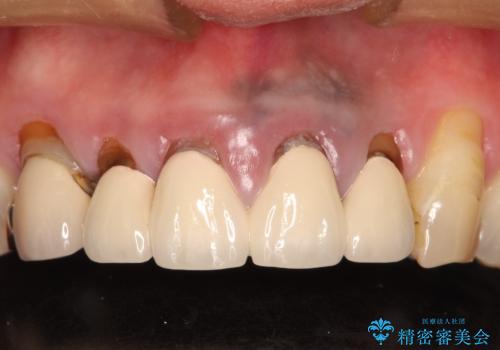

- 上の前歯の根元が黒くなっているので、再治療をしたいとのことで来院された患者様です。

レントゲンを撮影すると、適合不良のかぶせ物が装着されており、根の治療も不十分であることが確認されました。

適合不良のかぶせ物をすべて除去して、根の中の治療から再治療を行うこととなりました。

適合不良のかぶせ物が装着されていた歯は、内部がやはり虫歯になっていました。